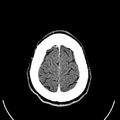

وللحصول على صورة أشعة مقطعية، يرقد المريض على طاولة تمر من خلال آلة فحص دائرية، تسمى المِسْند. وتوضع الطاولة بحيث يكون العضو المراد فحصه واقعًا عند منتصف المسند. وعن طريق أنبوب على المسند، تخرج أشعة سينية مخترقةً جسد المريض، ثم تدخل إلى مكشافات خاصة تقوم بتحليل الصورة التي ظهرت. ويدور المسند حول المريض للحصول على كثير من الصور من زوايا مختلفة. وبعد ذلك، يعالج الحاسوب المعلومات الآتية من المكشافات، لينتج صورة مقطعية مستعرضة على شاشة فيديو. وعن طريق تحريك الطاولة داخل المسْند، يمكن للأطباء الحصول على العديد من الفحوص للعضو نفسه، أو للجسد كله.

داخل الجهاز على شكل كعكة الدونات، حيث يستلقي المرضى على الطاولة بينما يتحرك ببطء عبر الماسح الضوئي، تدور الآلة حولها. أثناء دورانه، يرسل شعاعاً رفيعاً من الأشعة السينية عبر الجسم، والذي يتم جمعه على الجانب الآخر من الجهاز ونقله إلى برنامج حاسوب، حيث يتم تحميله على شاشة لعرضها على تقنيي التصوير المقطعي المحوسب.

يتحول إلى صورة مقطعية أو مسح ضوئي أو "شريحة" لجسم الإنسان، ويستغرق في بعض الجلسات أقل من 15 دقيقة لإكمال الفحص بالأشعة المقطعية. لقد أصبحت ممارسة طبية موثوقة وروتينية على مر السنين. من عام 1996 إلى عام 2010، تضاعفت معدلات التصوير المقطعي المحوسب ثلاث مرات، مما أدى إلى إضافة ما يصل إلى 149 فحصاً لكل 1000 مريض يدخلون المستشفى.[2]